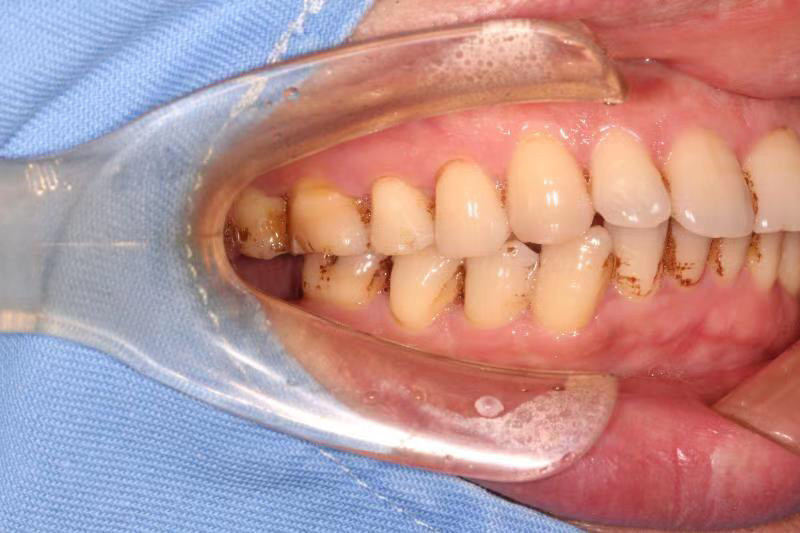

今天给大家介绍一个单颗后牙即拔即种病例。

患者中年男性,右下7号牙龋坏未及时处理至残根无法修复,CT检查发现骨量尚可,可以即拔即种,并且不需要植骨,节省了患者治疗周期,整个治疗过程用了4个月患者就戴上了牙齿。